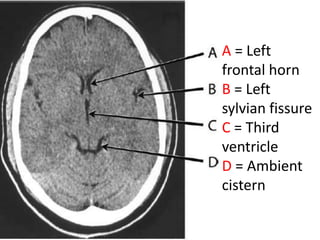

A = Left

frontal horn

B = Left

sylvian fissure

C = Third

ventricle

D = Ambient

cistern